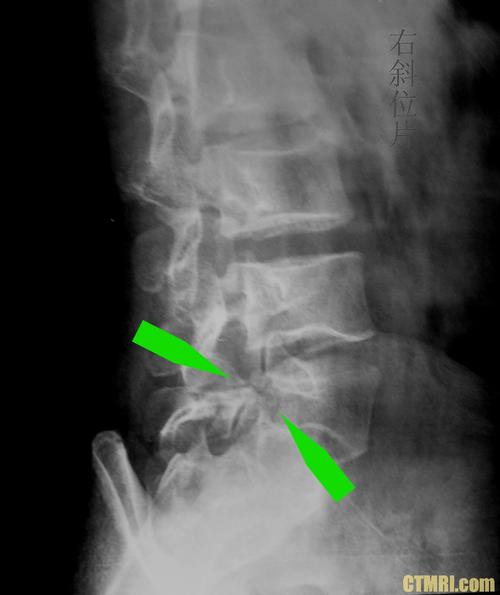

腰椎4一5节滑脱图

腰椎4一5节滑脱图,腰椎滑脱1度图片

收藏丨腰椎滑脱程度的等级清晰图解

腰椎滑脱症综述附图解

腰椎滑脱图片示意图

腰椎滑脱一二三四度图

腰椎滑脱的图片

腰椎滑脱图片

腰椎滑脱图片怎么看